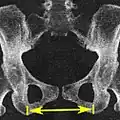

Размеры и форма таза имеют важное значение для родового процесса и подлежат измерению и оценке у всех беременных. Для определения внешних размеров таза у живого человека пользуются измерительным инструментом — тазомером Мартина, внутренние размеры выясняются расчётными методами исходя из внешних, также применяется мануальное исследование через влагалище и ультразвуковые исследования. Рентгенологические исследования, в том числе компьютерная томография, у беременных применяются в исключительных случаях для уточнения в виду нежелательного влияния ионизирующего излучения на плод и красный костный мозг женщины[1].

Размеры таза (в скобках у мужчин)[2]:

- Distantia interspinosa — между верхними передними подвздошными остями — 23-25 (21-23) см

- Conjugata anatomica или diameter recta (анатомическая конъюгата/прямой диаметр верхней апертуры) — между мысом крестца и верхним краем лобкового симфиза — 11,5 (10,8) см

- Diameter transversa (поперечный диаметр верхней апертуры) — наиболее отдалённое между пограничными линиями — 13,5 (12,8) см

- Diameter obliqua (косой диаметр) — между расположенными с противоположных сторон крестцово-подвздошным суставом и подвздошно-лобковым возвышением — 12,0-12,6 (12,0-12,2) см

- Прямой размер таза — между стыком II и III крестцовых позвонков и задней частью середины лобкового симфиза — 12,2 (10,8) см

- Поперечный размер таза — между центрами вертлюжных впадин — 11,5 (10,8)

- Прямой диаметр нижней апертуры — между вершиной копчика и нижним краем лобкового симфиза — 9,5 (7,5)

- Поперечный диаметр нижней апертуры — между седалищными буграми — 10,8 (8,1) см

- Угол наклона таза - угол между горизонтальной плоскостью и плоскостью верхней апертуры таза

- Distantia intercristalis — между подвздошными гребнями тазовых костей — 25-27 см

- Distantia intertrochanterica — между большими вертелами бедренных костей — 28-29 см

- Conjugata vera (истинная гинекологическая конъюгата) — между мысом крестца и самой задней точкой лобкового симфиза — 10,5-11,0 см

- Conjugata diagonalis (диагональная конъюгата) — между мысом крестца и нижним краем лобкового симфиза — 12,5-13,0 см.

Измерение размеров на томограмме низкодозовой компьютерной томографии